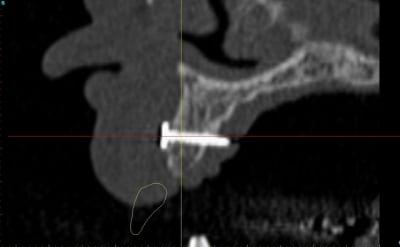

Dar axial lebnbu - Eugenol

Dar axiali qui1is - Eugenol

Dar11 cyo3el - Eugenol

Dar13 alznrp - Eugenol

Dar13i aujibg - Eugenol

Dar14 actm24 - Eugenol

Dar15 zvi82y - Eugenol

Dar23i g6nxds - Eugenol

Dar24 vzfroa - Eugenol

Dar25 lcptyk - Eugenol

Dar 3d xkb3uv - Eugenol

Dar  3di ngfcc4 - Eugenol

Dar  3dl fwmdk6 - Eugenol

Céramik

image 8, il semble y avoir une zone entre le greffon et l'os ?

C'est intégré ?